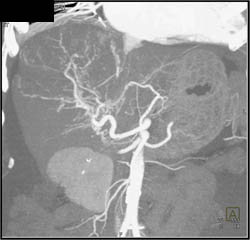

Hepatoma With Neovascularity